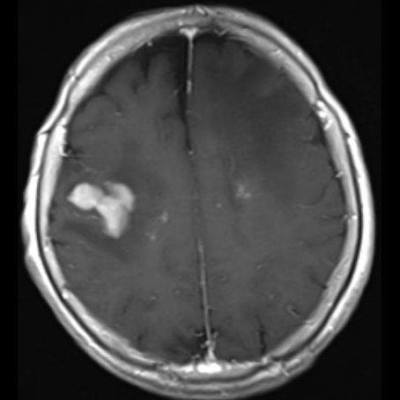

- (B) Aksiyel postkontrast T1A görüntülerde büyüğü sol frontalde kontrastlanma gösteren multipl kitle lezyonları (oklar) izlenmektedir.

- Olguda tanı sol frontalde kontrast tutan lezyondan yapılan beyin biyopsisi ile konulmuştur.

- Genellikle supratentoriyal alanda, bazal ganglion, periventriküler beyaz cevher, orta hat ve korpus kallozum vb. yerleşme eğiliminde tek veya multipl kitleler şeklinde görülür.

- Kitleler çoğunlukla solid ve homojendir.